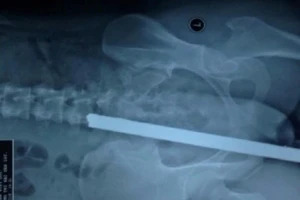

Cấp cứu 1 bệnh nhân bị thanh sắt đâm vào mông